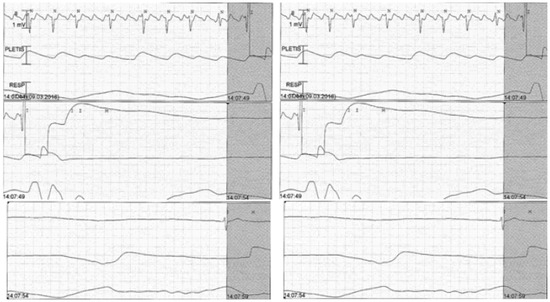

Transthoracic echocardiography (TTE) revealed mild left ventricular hypertrophy with normal systolic function. We decided to schedule the patient for electric cardioversion and we started oral anticoagulation (rivaroxaban 20 mg). After the first electric shock, there was a sinus arrest lasting 15 seconds, without ventricular escape rhythm (Figure 2).

Figure 2.

ECG monitoring showing sinus arrest (15 seconds) after electric cardioversion.